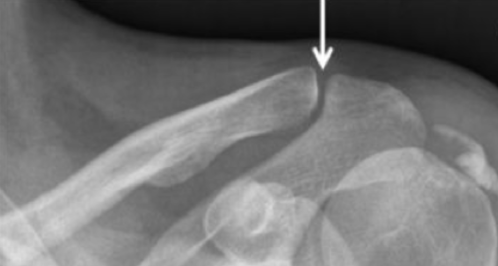

La luxation : outre la douleur locale, on observe une « touche de piano ».

Stade I

Entorse acromio-claviculaire simple avec distension sans rupture des ligaments acromio-claviculaires. Pas d’instabilité

Stade II

Subluxation acromio-claviculaire avec rupture des ligaments acromio-claviculaires, les ligaments coraco-claviculaires étant distendus mais non rompus. Petit bâillement de l’articulation (discrète mobilité de haut en bas) sans mobilité anormale antéro-postérieure

Stade III

Luxation acromio-claviculaire complète par rupture complète des ligaments acromio-claviculaires et coraco-claviculaires. Déformation visible avec saillie de l’extrémité externe de la clavicule pouvant être réduite par simple pression (touche de piano). Il existe en outre une mobilité antéro-postérieure (tiroir antéro-postérieur)